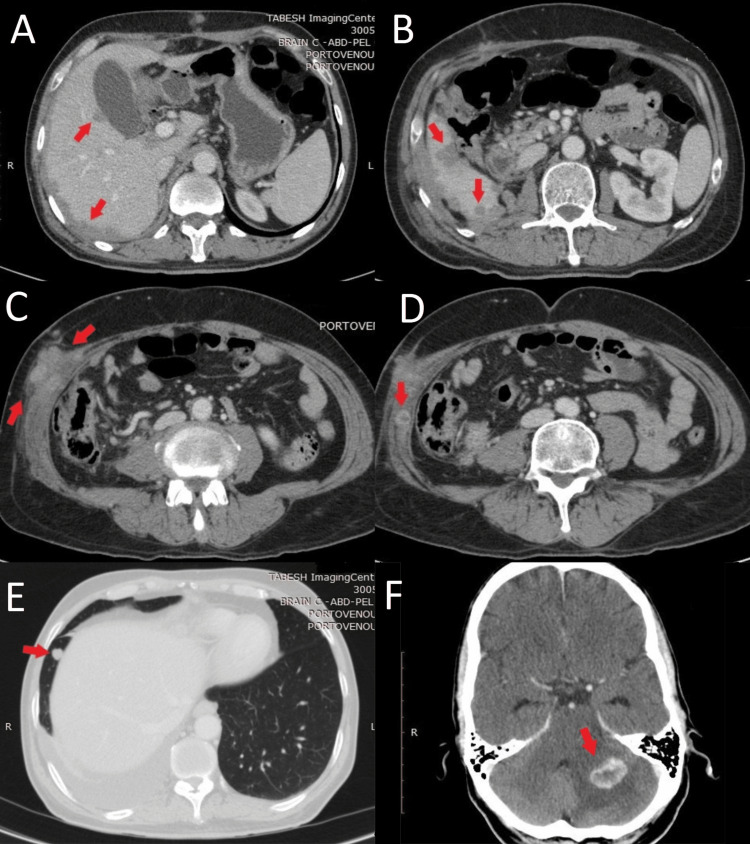

Open right radical nephrectomy was performed in November 2019 and the histopathologic diagnosis revealed clear cell type RCC with massive necrosis and no sarcomatoid differentiation along with invasion to the renal pelvis, adrenal gland, omental fat, and diaphragm. Accordingly, the patient was commenced on adjuvant sunitinib 50 mg on the 3/1 schedule (50 mg once daily for three consecutive weeks on treatment followed by one-week-off). Following four months of treatment with sunitinib, the patient became icteric and developed a progressive headache. Further evaluations discovered multiple masses in the renal fossa and abdominal wall, multiple round lesions in the right hepatic lobe, and a few right pleural-based nodules. He was also found to have two enhancing lesions (20×15 mm and 5×3 mm) in the posterior fossa of the brain consistent with metastatic disease (Figure 2).

Due to the failure of first-line treatment with sunitinib, treatment was switched to nivolumab 3 mg/kg (240 mg) administered every two weeks. He also received palliative whole-brain radiation therapy (WBRT) to a total dose of 35 Gy delivered during 14 fractions. After four months of treatment with nivolumab, fluorodeoxyglucose (FDG) – positron emission tomography (PET)/CT scan was obtained and it revealed complete resolution of metastatic lesions in the brain and lungs as well as a reduction in the size and the number of lesions in the liver, without the appearance of any new lesions (Figure 3).